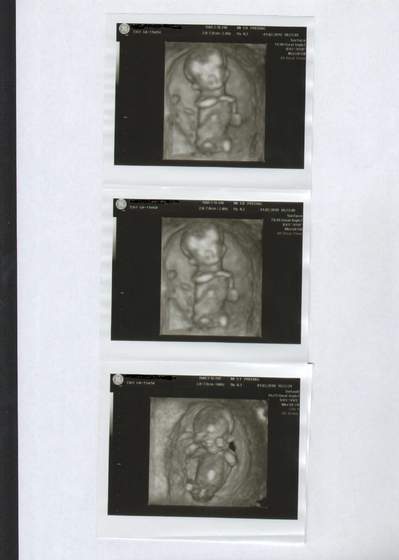

Super, że dzieciaczek zdrowy i po krwiaku nie ma śladuja dzisiaj foty nie dostałam ale pal nicho wazne, że wszystko ok i nie ma krwiaka! zginęła mara okropna!dzieciak zdrowy, sprawny etc. :-)